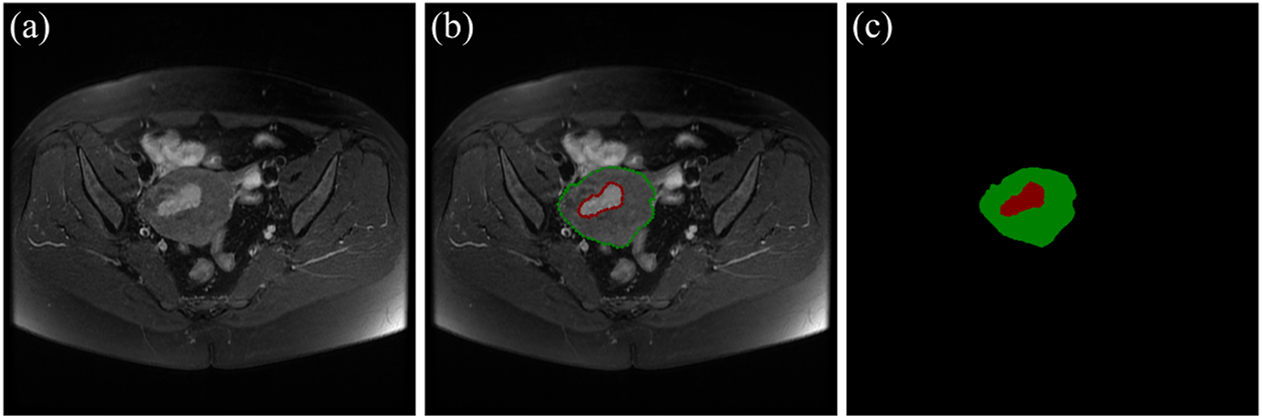

There are 117 patients with early EC in the data sets, including 73 cases of stage IA and 44 cases of stage IB. An experienced radiologist selected the slices that clearly visualizes the uterus and tumor from each patient’s three different MRI sequences. As a result, 455 MRI images (161 axial T2WI images, 161 axial DWI images, 133 sagittal T2WI images) are obtained. According to the convention of deep learning model training, the dataset is divided in the ratio of 6:1:3 (Andrew, 2018; Jayapandian et al., 2021) The selected MRI images are randomly separated into 70 cases (44 IA/26 IB) including 272 images as the training set, 12 cases (7 IA/5 IB) including 46 images as the validation set, and 35 cases (22 IA/13 IB) including 136 images as the test set. The details of data sets are shown in Table 3. The uterus and tumor on the above MRI images were manually segmented by the experienced radiologist through the software LabelMe (Russell et al., 2008). These segmented areas were used as the ground truth for uterus and tumor segmentation. An original MRI image and the corresponding segmented image are shown in Figure 2.

FIGURE 2

www.frontiersin.org

FIGURE 2. (A) The original MRI image. (B) The original MRI image with ground-truth contours of the uterus and tumor, where the red outline is the ground-truth of the tumor and the green outline is the ground-truth of the uterus. (C) The label image that LabelMe transforms from the ground-truth contours in (B) which is used for DL model training.